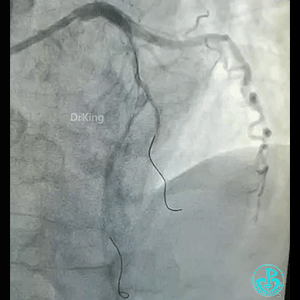

导丝怎么扩真怪!急性心梗前降支导丝通过顺利,球囊扩张后导丝移位很多!不在原来的血管腔!_https://www.jmylbn.com_新闻资讯_第3张

再进一根导丝,可以在对角支和主支随意进出,随后病人血流变慢,症状有加重,后面的造影血流更慢。